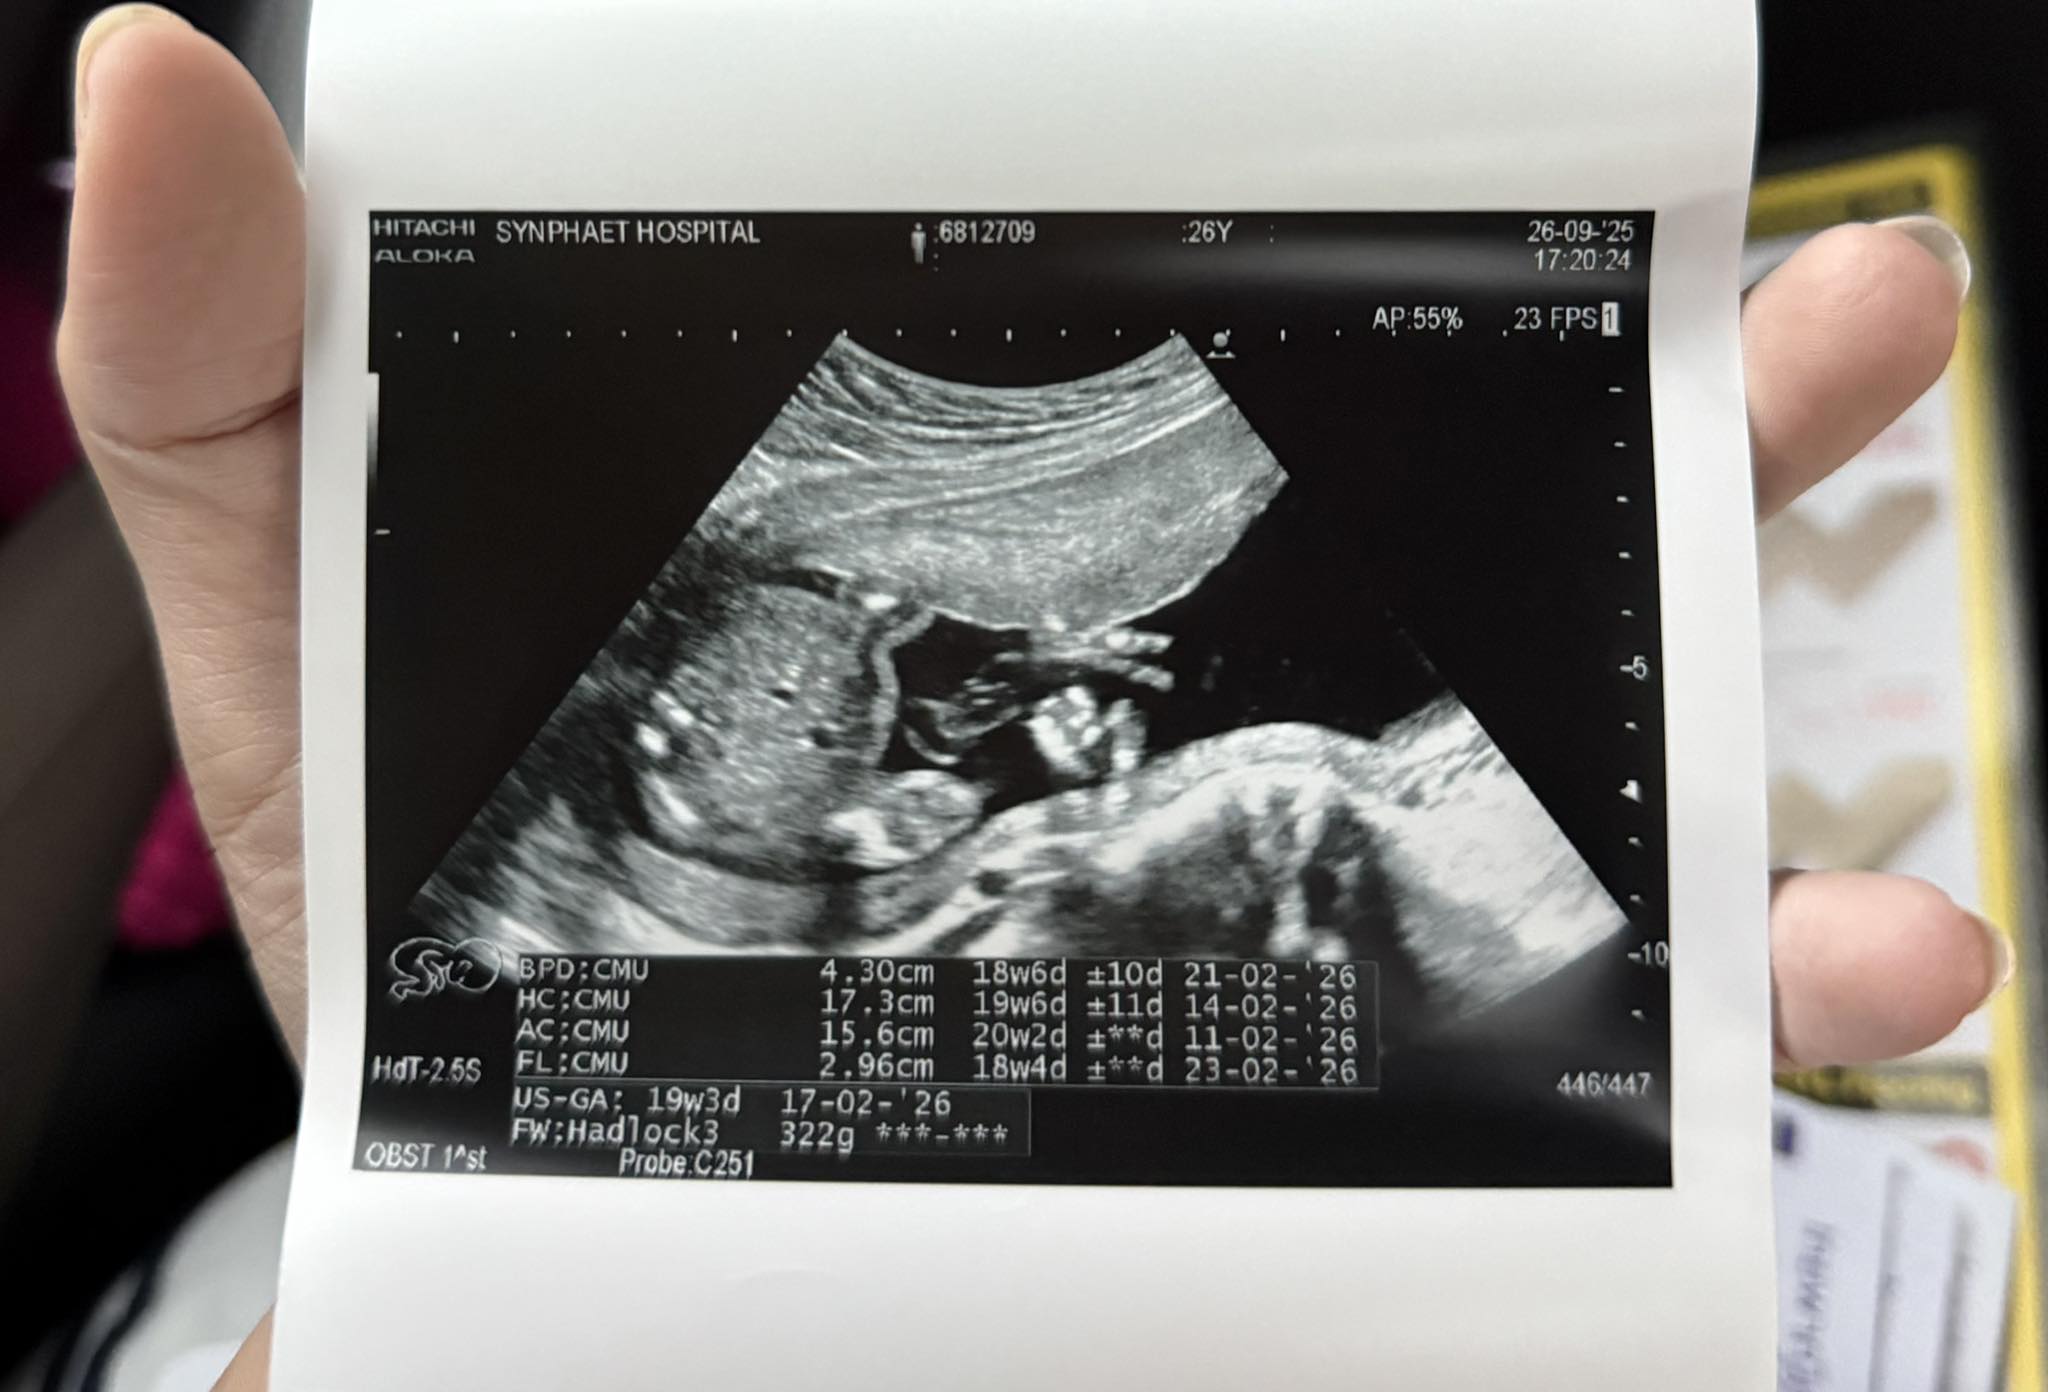

ก็เลยตัดสินใจไปหาคุณหมอที่ฝากครรภ์ แล้วคุณหมอก็ได้อัลตร้าซาวด์ ได้ผลสรุปว่า”มดลูกบีบตัว“

ซึ่งมันไม่ควรที่จะเกิดขึ้นกับคนท้องระยะคันประมาณ 4-5 เดือน แต่มันควรจะเกิดขึ้นสำหรับคนท้องอายุครรภ์7-8 เดือน

คุณหมอเลยให้งดให้เดินทางไกล งดยืนนานๆ งดการขยับเร็ว และให้ใส่ผ้าพยุงครรภ์ไว้

เนื่องจากกลัวว่าจะมีผลกระทบต่อเบบี๋ในครรภ์ เพราะอาจจะเสี่ยงคลอดก่อนกำหนด แล้วคุณหมอก็ให้ยามาทานแล้วค่ะ แต่อาการยังไม่หาย..